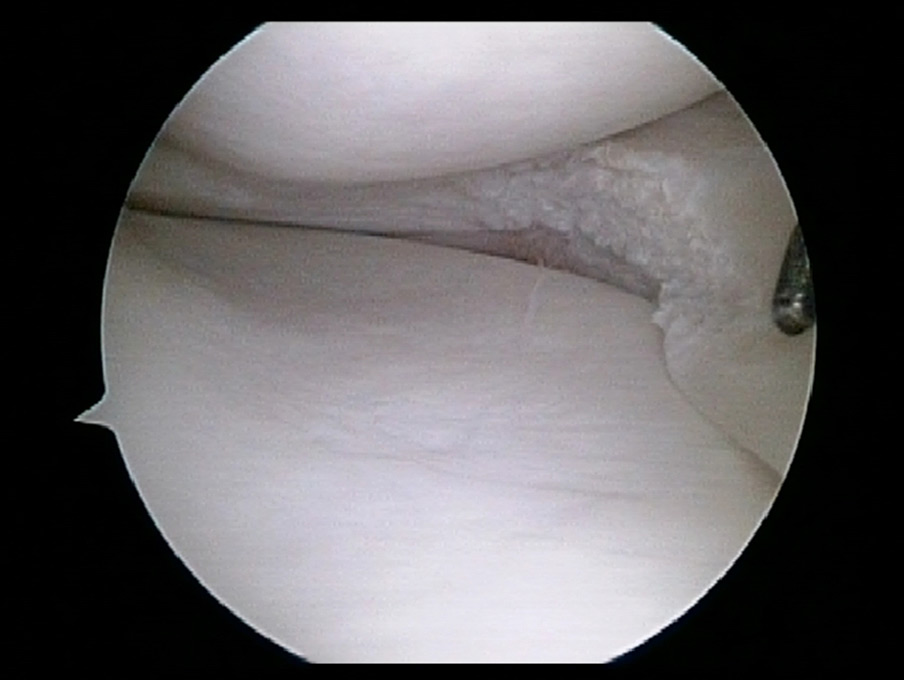

Meniscus knee meniscus meniscus anatomy cartilage tears meniscus injury lateral rotation knee articular cartilage injury to the knee torn meniscus articular cartilage. See meniscus tear stock video clips. Knee arthroscopy, a minimally invasive procedure, is often used to treat meniscal tears. The torn meniscus is repaired by a variety of minimally invasive techniques and requires postoperative protection to allow healing. The first choice for professional athletes worldwide. Meniscus surgery is a common operation to remove or repair a torn meniscus, a piece of cartilage in the knee. The tear of the meniscus is situated in the posterior half (of the meniscus). The meniscus also becomes softer with age, making it easier to tear.

Meniscus surgery is a common operation to remove or repair a torn meniscus, a piece of cartilage in the knee. Knee arthroscopy, a minimally invasive procedure, is often used to treat meniscal tears. Fda registered class i & ii medical devices for home use. What is the healing time for a meniscus tear? The tear of the meniscus is situated in the posterior half (of the meniscus).